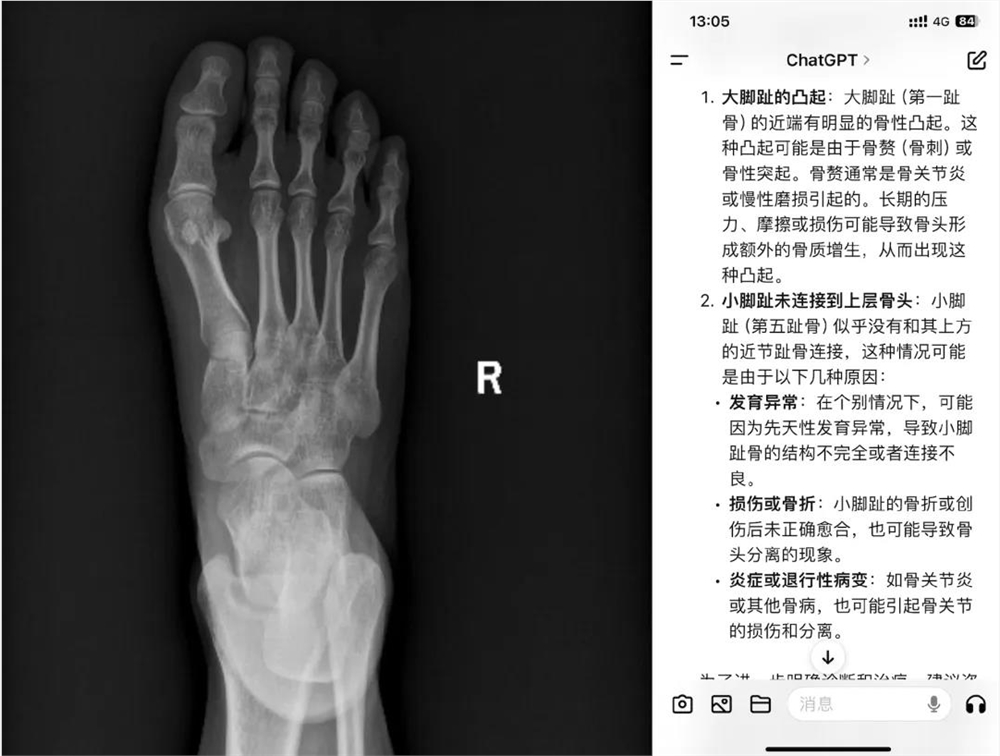

此前有网友让GPT-4o做微表情观察专家,让通义千问评价工作餐属于什么水准,甚至生活中拍完的骨科片子也让AI给出意见。

这些场景下,AI又成了“互联网冲浪吃瓜搭子”、“工作用餐时的吃饭搭子”,以及“看病搭子”。